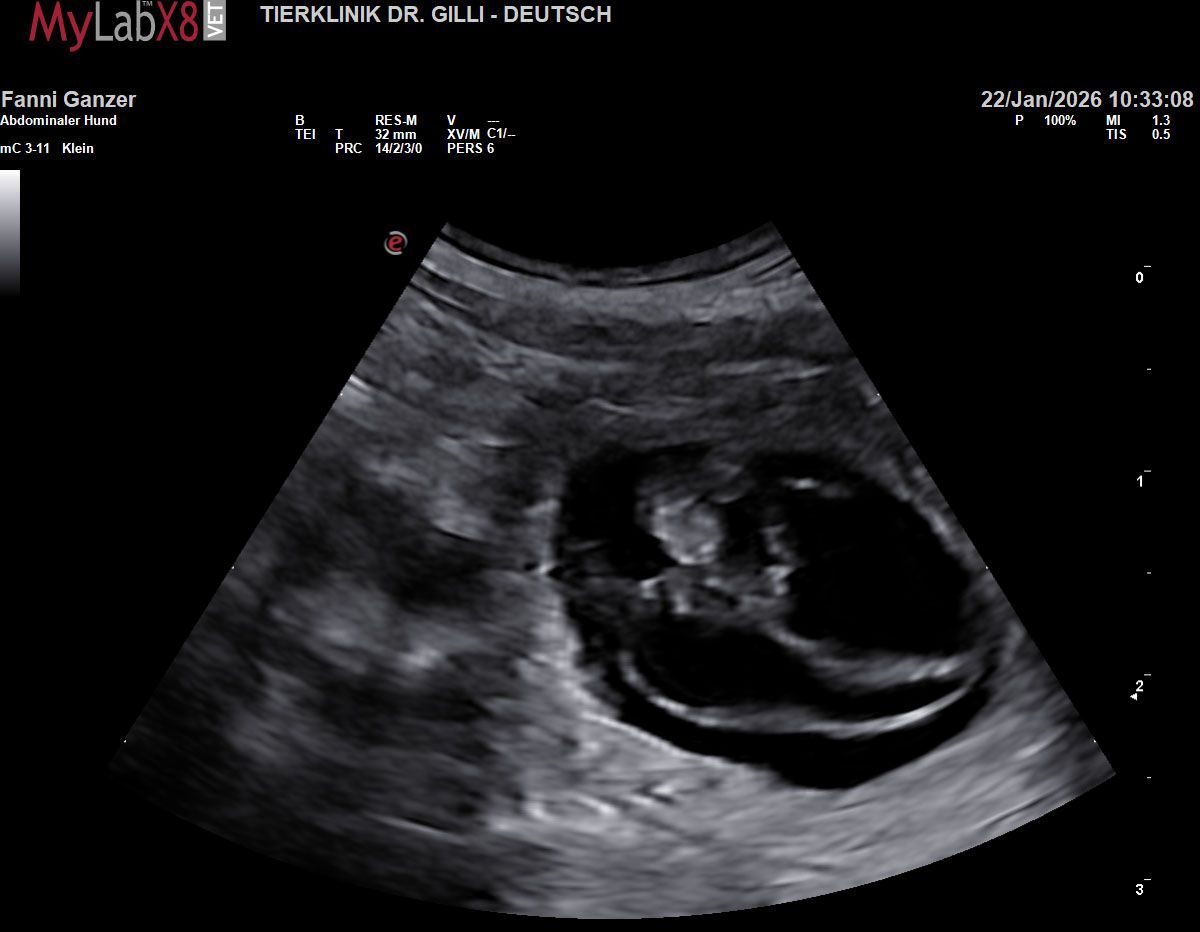

Die nächste Generation von Of Green Spirits hatte ihren ersten „Fototermin“! Gestern wurde durch unsere Tierärztin offiziell bestätigt, was wir bereits gehofft hatten: Unsere Bourbon Vanille of Green Spirits (Fanni) und Amico Terrier's Nougat Wafer (Wafer) werden Eltern.

Unser gemeinsamer Ausflug nach Venedig zum Jahresende trägt nun buchstäblich Früchte. Beim Ultraschall konnten wir bereits 3 bis 4 kleine, gefüllte Fruchtblasen zählen. Wie bei jedem Wurf unserer Zucht ist die Aufregung im Hause Of Green Spirits riesig. Wir blicken voller Vorfreude auf die kommenden Wochen und können es kaum erwarten, die nächste Generation unserer Welpen gesund und munter bei uns willkommen zu heißen.